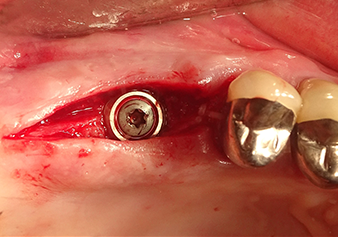

Una paziente di 49 anni, non fumatrice e con un'anamnesi priva di elementi rilevanti, è stata indirizzata al nostro studio di chirurgia orale per l'estrazione chirurgica del dente 16 ed il successivo impianto. Dopo l'estrazione, la paziente ha accusato dei lievi dolori causati dalla sinusite, motivo per cui abbiamo inizialmente aspettato sei mesi prima di procedere con l'intervento. L'altezza ossea residua in corrispondenza della posizione dell'impianto misurava 3-4 mm (Fig. 1 e 2).

Sono gli strumenti a svolgere il lavoro

Dopo la preparazione atraumatica del lembo mucoperiosteo, con l'ausilio dello strumento I1 è stata contrassegnata la posizione e preparata la sede dell'impianto fino ad avvertire la resistenza iniziale. Gli strumenti piezochirurgici sono stati utilizzati eseguendo un movimento verticale ascendente e discendente senza dover esercitare alcuna pressione. La vibrazione piezoelettrica ha generato la cavitazione richiesta ad elevata efficienza.